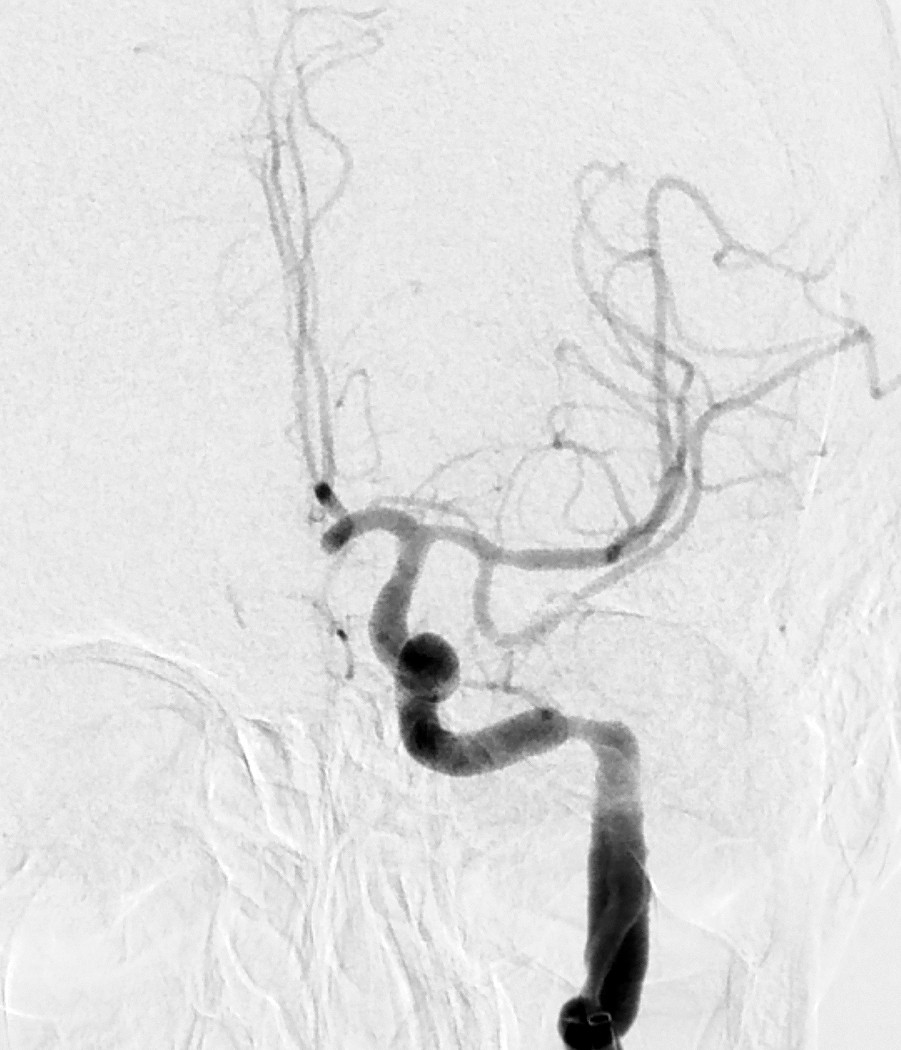

Myren-Svelstad S, Hammer TA, Idicula TT. Early thrombectomy of a proximal middle cerebral artery occlusion leading to complete recovery with no infarct. Case Rep Neurol 2017; 9: 76 - 80. [PubMed][CrossRef]

Vi vil takke for en fin kasuistikk som til fulle viser hvilket potensiale mekanisk rekanalisering (trombektomi) har ved cerebral storarterieokklusjon. Antall som må behandles for én pasient skal komme gjennom et hjerneinfarkt med mindre grad av funksjonshemming (Number Needed to Treat, NNT), er 2,6. I Norge gjennomføres trombektomi per dags dato ved fem sykehus, og to nye sykehus skal starte med trombektomi fra neste år.

Ved St. Olavs Hospital synes man å ha en meget konservativ utvelgelse av pasienter for trombektomi. Forfatterne skriver at behandlingen vanligvis ikke gjøres ved NIHSS-skår < 10. Vi mener i overenstemmelse med publiserte metaanalyser at en slik høy grense for intervensjon gjør at endel pasienter går glipp av svært viktig akuttbehandling. Målet med trombektomi er å begrense skadevolumet i hjernen, ikke å reperfundere et hjernevolum som allerede er nekrotisk. Ved de andre trombektomi-sentrene i Norge vektlegges derfor CT/MR penumbra-vurdering, kollateralsirkulasjon og eventuelt diffusjonsfunn på MR sterkere enn selve NIHSS-skåren når indikasjonen for trombektomi stilles. I OUS-materialet fra 2017 hadde 39 av totalt 120 pasienter (32,5 %) NIHSS-skår < 10 på indikasjonstidspunktet (abstrakt presentert på Nevrodagene 2018 ved B. Enriques og medforfattere). Disse hadde klinisk og radiologisk et stort truet penumbravolum. Ved å bruke høy NIHSS-skår som indikasjon og ikke en individuell fysiologisk tilnærming vil trolig for få pasienter bli behandlet og det samlete resultatet etter trombektomi bli vesentlig dårligere enn det kunne ha vært.

Vi takker Anne Hege Aamodt og medarbeidere for en hyggelig og viktig kommentar. Beklageligvis ligger pasientkasuistikken noe tilbake i tid, utarbeidelse av manuskript likeså. I Trondheim benyttes CT/MR for vurdering av penumbra og kollateralsirkulasjonen vektlegges. At NIHSS-skår ikke kan benyttes som indikasjon alene er selvsagt, og denne misforståelsen beklager vi. Samtidig bør det være et visst nevrologisk utfall før en invasiv prosedyre utføres. Ved St. Olavs hospital gjøres i dag normalt ikke trombektomi ved NIHSS-skår ≤ 5, men alle pasienter som kan være kandidat til trombektomi, får en individuell vurdering, også de med lavere NIHSS-skår.